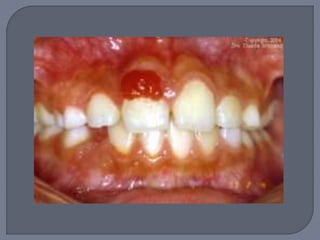

Lesión elevada localizada de tejido de

granulación

Aparece en diversas áreas de la mucosa y piel,

siendo la encía la localización más común

junto con labios y dorso de la lengua

Masa exofítica a veces lobulada y ulcerada

Por lo general pedículada

Color rojo o rojo púrpura

Tendencia a sangrado

Diámetro de milímetros a centímetros